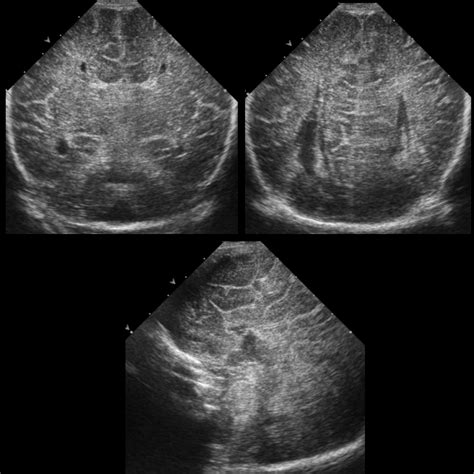

Diagnosis typically occurs through medical imaging, often initiated by a pediatrician or neurologist when developmental delays are noted. Because the condition is structural, standard imaging is the primary diagnostic tool used by clinicians.

Fetal Ultrasound Prenatal screening Moderate, can miss subtle cases.